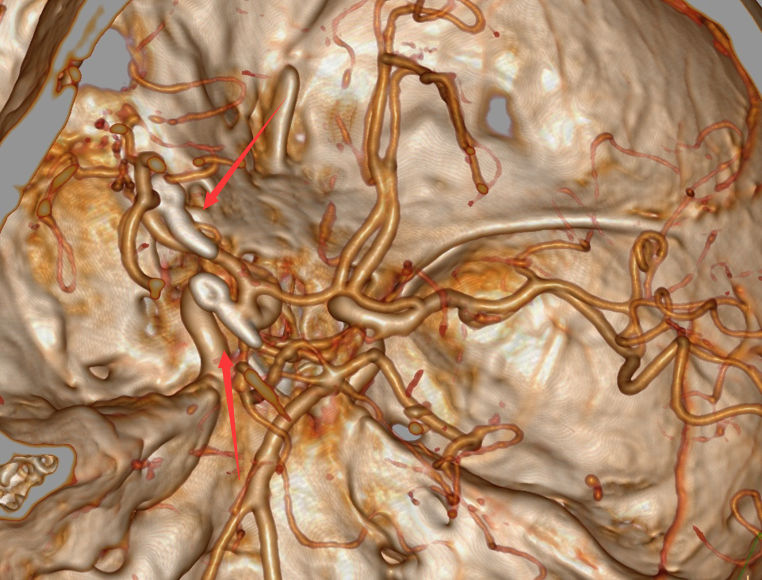

术后CTA复查影像显示动脉瘤夹闭良好,相关血管保留良好,箭头所指为动脉瘤夹位置。

箭头所指为血管同侧的另一个动脉瘤。

箭头所指为患者病灶处,动脉瘤大小仅1毫米,在造影上几乎微不可见。